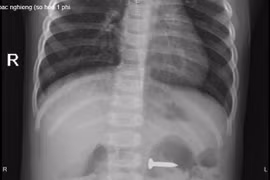

(GLO)- Ngày 14-12, Bệnh viện Sản Nhi tỉnh Phú Thọ cho biết, các bác sĩ khoa Cấp cứu đã tiếp nhận và kịp thời gắp 1 chiếc đinh vít sắc nhọn trong dạ dày bé N.P.C. (2 tuổi, trú tại huyện Lập Thạch, tỉnh Vĩnh Phúc).